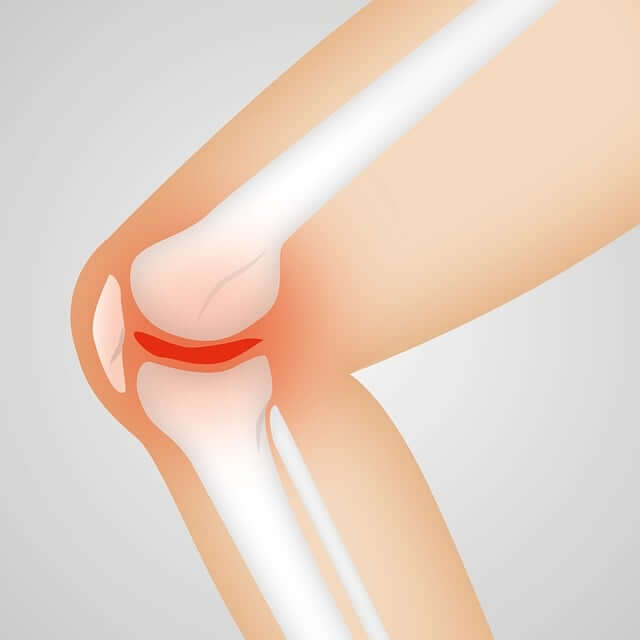

뼈를 연결하고 움직임을 가능하게 하는 관절은 문제가 발생할 때까지 그다지 눈에 띄지 않는 것이 특징입니다. 결국 불편함이나 통증을 느끼고 나서야 이상이 생겼음을 인지하게 됩니다.

관절 건강을 위한 방법을 이해하려면 관절의 복잡한 해부학적 구조를 먼저 알면 도움이 됩니다.

■ 관절은 두 개 이상의 뼈가 만나는 지점으로 무릎 및 팔꿈치와 같은 경첩 관절, 엉덩이와 어깨에 있는 볼-소켓 관절, 목에서 볼 수 있는 피벗 관절, 손목의 활주 관절 등이 있습니다.

■ 관절 건강의 핵심은 뼈 끝을 덮고 있는 연골에 영양을 공급하는 투명하고 점성 있는 액체인 윤활액이라고 할 수 있습니다. 이 윤활핵은 천연 충격 흡수 장치 역할을 하여 마찰을 줄이고 관절 표면의 마모를 방지하며 관절의 움직임을 보다 부드럽고 원활하게 하고 부상 위험도 최소화 해줍니다.

■ 연골은 관절 내에 있는 뼈의 끝부분을 덮는 완충재 역할로 뼈가 미끄러질 수 있는 매끄러운 표면을 제공하여 마찰을 줄이고 무게를 고르게 분산시킵니다. 나이가 들어도 통증이 없는 부드러운 관절 이동성을 위해서는 건강한 연골이 큰 역할을 합니다.

■ 인대는 뼈와 뼈를 연결하고 힘줄은 근육을 뼈에 연결합니다. 이러한 결합 조직은 움직임에 안정성을 제공하고 원하는 대로 움직임을 제어할 수 있게 합니다. 관절을 둘러싸고 있는 강하고 상태가 좋은 근육은 지지와 보호를 제공해 관절의 안정성을 유지하는 데 중요한 역할을 합니다.